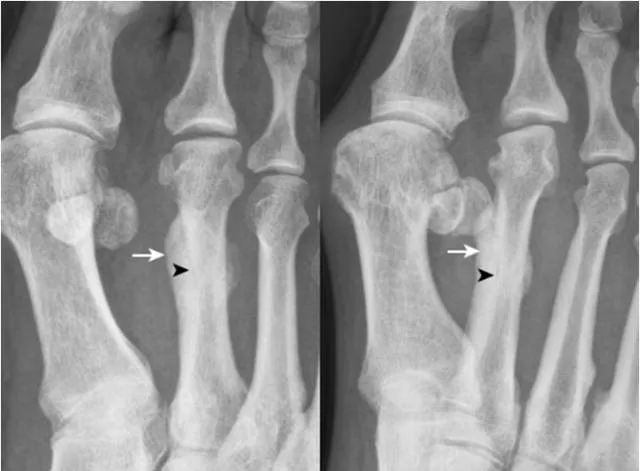

33.籽骨骨折:

拇趾外侧籽骨形态不完整,内侧见透亮线(箭),两部分骨对应缘不规整,无硬化缘,与二分籽骨的边缘骨质致密不同。内侧籽骨完整(箭头)。